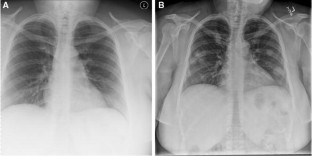

Benign Metastasizing Leiomyomas Following Myomectomy and Uterine Artery Embolization

Benign metastasizing leiomyomas (BMLs) are rare sequelae of common uterine leiomyomas and most frequently found in the lungs. Most cases of BMLs occur with a history of prior gynecologic procedures; however, none have yet been reported in association with uterine artery embolization (UAE). This case report highlights the disease course for a 48-yo female with a history of both myomectomy and UAE for uterine fibroids who presented later with bilateral pulmonary BMLs. Though the pathophysiology of BMLs is poorly understood and this case is confounded by prior myomectomy, it does bring into question whether UAE has a role in BML development. Regardless, UAEs have become a routine procedure and interventionalists should be aware of the possibility of BMLs in post-fibroid treatment patient populations.

Fig. 1

Fig. 2

• Uterine fibroid embolization

• Benign metastasizing leiomyoma

• Pulmonary nodules